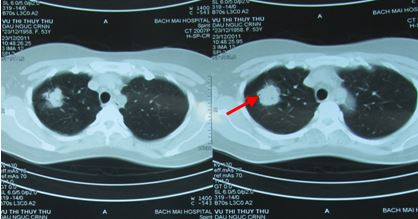

- Chụp CT scanner lồng ngực:

Hình 1: Hình ảnh chụp CT phổi trước điều trị cho thấy u phổi phải kích thước 3,4cm, ngấm thuốc mạnh sau tiêm

Hình 6: U phổi trước điều trị

Hình 7: U phổi sau điều trị 16 tháng, tổn thương xơ hóa nhỏ